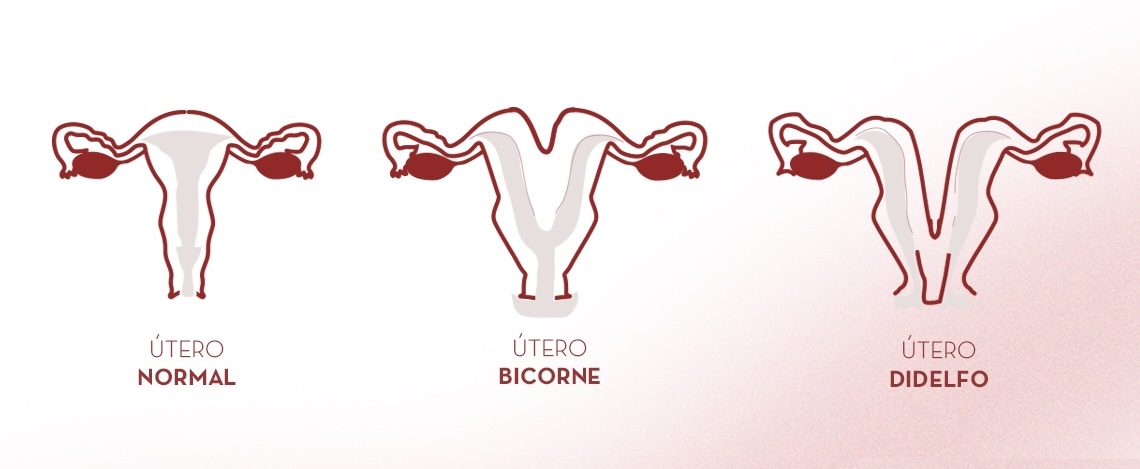

Las adhesiones intrauterinas son bandas de tejido fibroso que se forman dentro de la cavidad del útero, provocando que sus paredes se adhieran parcial o totalmente. Esta condición puede alterar la anatomía uterina normal y afectar la menstruación, la fertilidad y la salud reproductiva.

La causa más frecuente es una lesión del endometrio (revestimiento interno del útero), generalmente asociada a:

- Cirugías uterinas